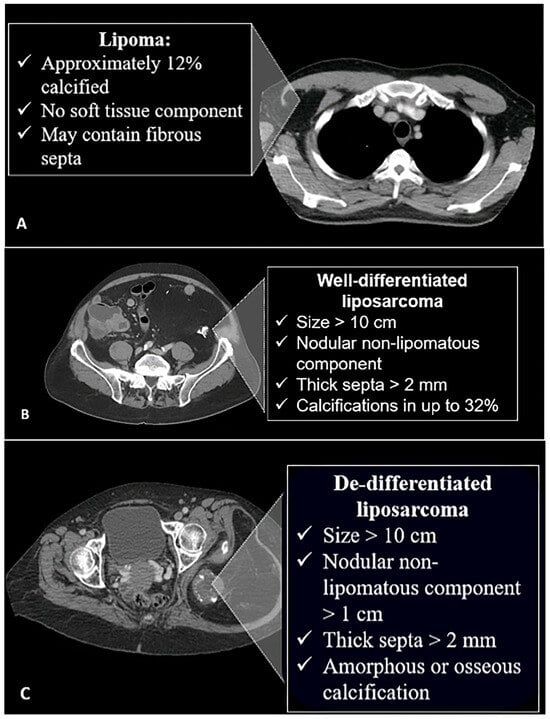

4.1. Adipocytic Tumors

- Peterson, J.J.; Kransdorf, M.J.; Bancroft, L.W.; O’connor, M.I. Malignant fatty tumors: Classification, clinical course, imaging appearance and treatment. Skelet. Radiol. 2003, 32, 493–503. [Google Scholar]

- Kransdorf, M.J.; Bancroft, L.W.; Peterson, J.J.; Murphey, M.D.; Foster, W.C.; Temple, H.T. Imaging of fatty tumors: Distinction of lipoma and well-differentiated liposarcoma. Radiology 2002, 224, 99–104. [Google Scholar]

- Murphey, M.D.; Arcara, L.K.; Fanburg-Smith, J. Imaging of musculoskeletal liposarcoma with radiologic-pathologic correlation. Radiographics 2005, 25, 1371–1395. [Google Scholar]

- Henze, J.; Bauer, S. Liposarcomas. Hematol. Oncol. Clin. 2013, 27, 939–955. [Google Scholar] [CrossRef]

- Toms, A.P.; White, L.M.; Kandel, R.; Bell, R.S. Low-grade liposarcoma with osteosarcomatous dedifferentiation: Radiological and histological features. Skelet. Radiol. 2003, 32, 286–289. [Google Scholar]

- O’Regan, K.N.; Jagannathan, J.; Krajewski, K.; Zukotynski, K.; Souza, F.; Wagner, A.J.; Ramaiya, N. Imaging of liposarcoma: Classification, patterns of tumor recurrence, and response to treatment. Am. J. Roentgenol. 2011, 197, W37–W43. [Google Scholar] [CrossRef]